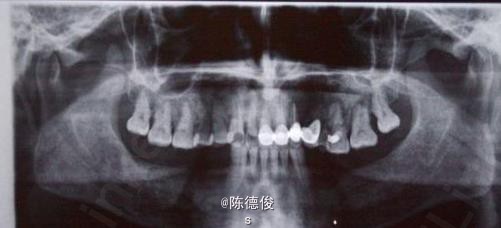

男,64岁,下颌多颗牙缺失数年,身体健康,无烟酒嗜好。

诊断:肯氏1类缺失 诊疗方案:种植固定桥修复+咬合重建 种植系统:瑞士ITI-Straumann种植系统 治疗周期:3个月